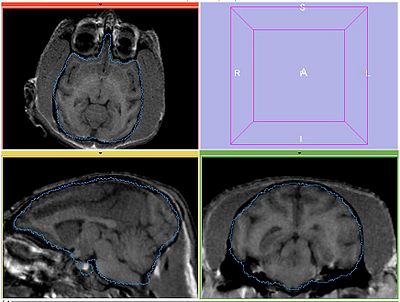

The following screeshots demonstrate good initial alignment of the images with the initial affine transformation, and the outline of ROIs. Also note that FIXED1 and FIXED2 are very similar within ROI.

FIXED2